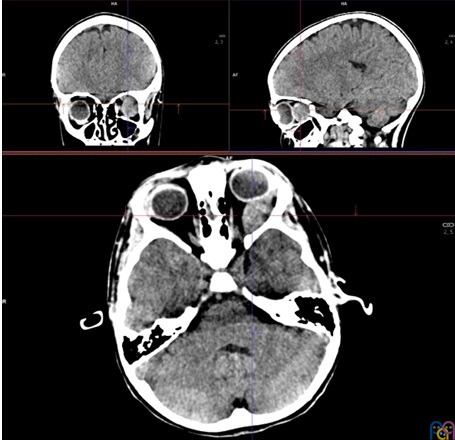

Es derivada a urgencias hospitalarias, donde se realiza TAC craneal sin contraste intravenoso que objetiva una lesión retrorbitaria izquierda de 28 x 14 mm, unilateral, aparentemente extraconal (Figura 1 y Figura 2), que condiciona proptosis, efecto de masa sobre estructuras retroculares y pérdida de esfericidad ocular; se cosidera como primera posibilidad diagnóstica rabdomiosarcoma vs. lesión vasculogénica (hemangioma infantil o malformación venolinfática).

Figura 1. TAC sin contraste: cortes axial, sagital y frontal

Figura 2. TAC sin contraste: corte sagital